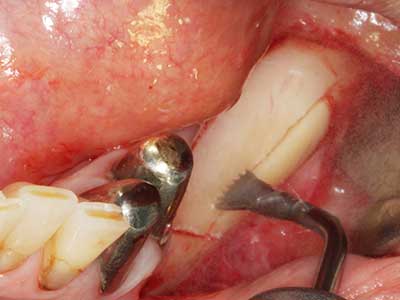

Индикация: Препарация близо до нерви

Когато се извършват хирургични процедури върху кост в непосредствена близост до чувствителни структури като кръвоносни съдове или нерви, ротиращите инструменти създават значителен риск за ятрогенно нараняване. Пиезоелектрическите апарати могат да бъдат от помощ при препарация на костно покритие и отстраняване на твърда кост близо до нерви, особено за оголване на нервите след ятрогенно нараняване, както и по време на латерализация на нервите за резекционни и реконструктивни процедури или поставяне на имплант (Фиг. 17-20). Лекият контакт между пиезонакрайника и нерва по принцип не води до нараняване, но ако действате непредпазливо с трионообразни движения или приставки за остатъчен костен субстрат, може да причините временно или перманентно увреждане на нерва. Въпреки това, рискът от увреждане се счита за много по-малък, отколкото при употреба на триони или ротиращи инструменти (Pereira, Gealh et al. 2014).